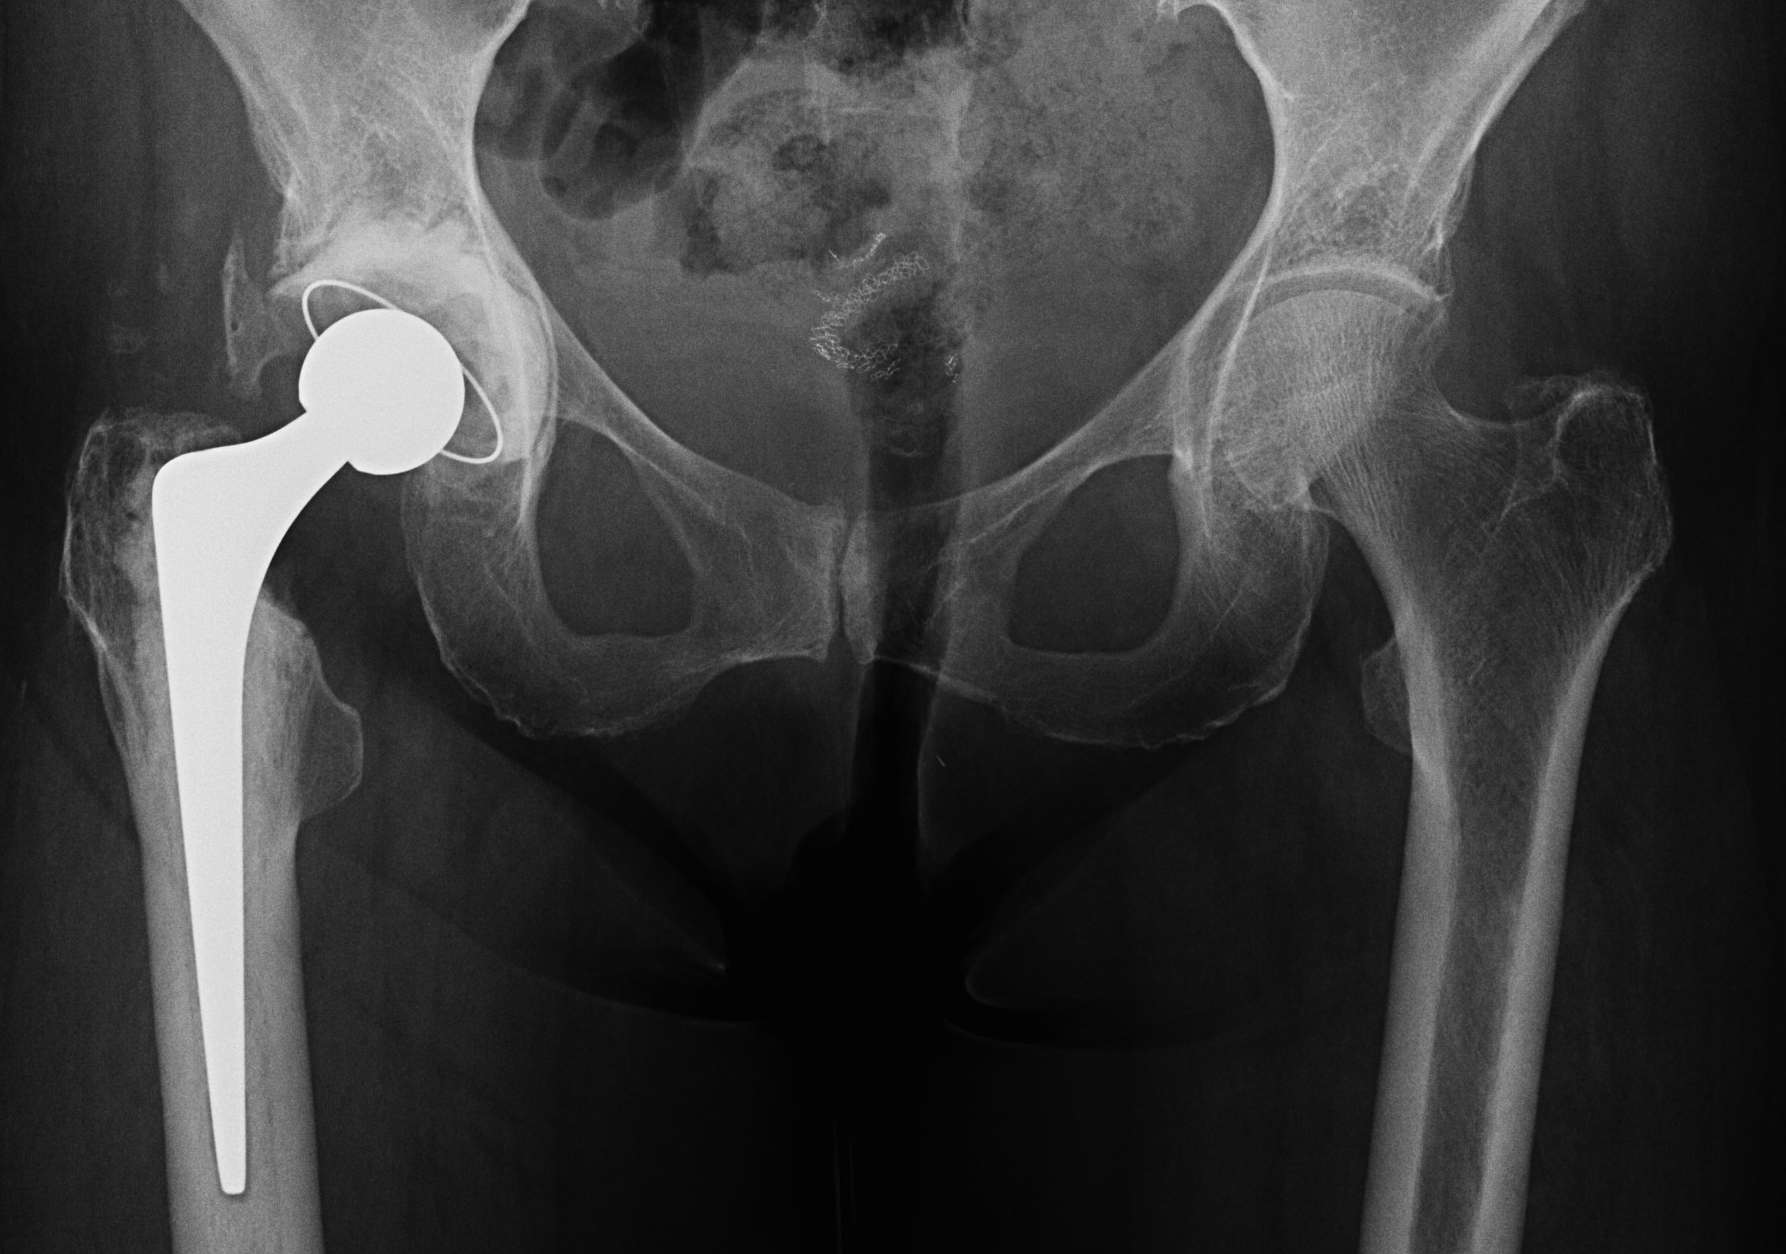

AP pelvis

- both femurs IR 15o / compensate for anteversion

- symmetrical abduction / adduction of femurs

Abnormal femur position

Pelvic landmarks

- inferior aspect of ischial tuberosities

- tear drop

- center of rotation

Femoral landmarks

- lesser tuberosity